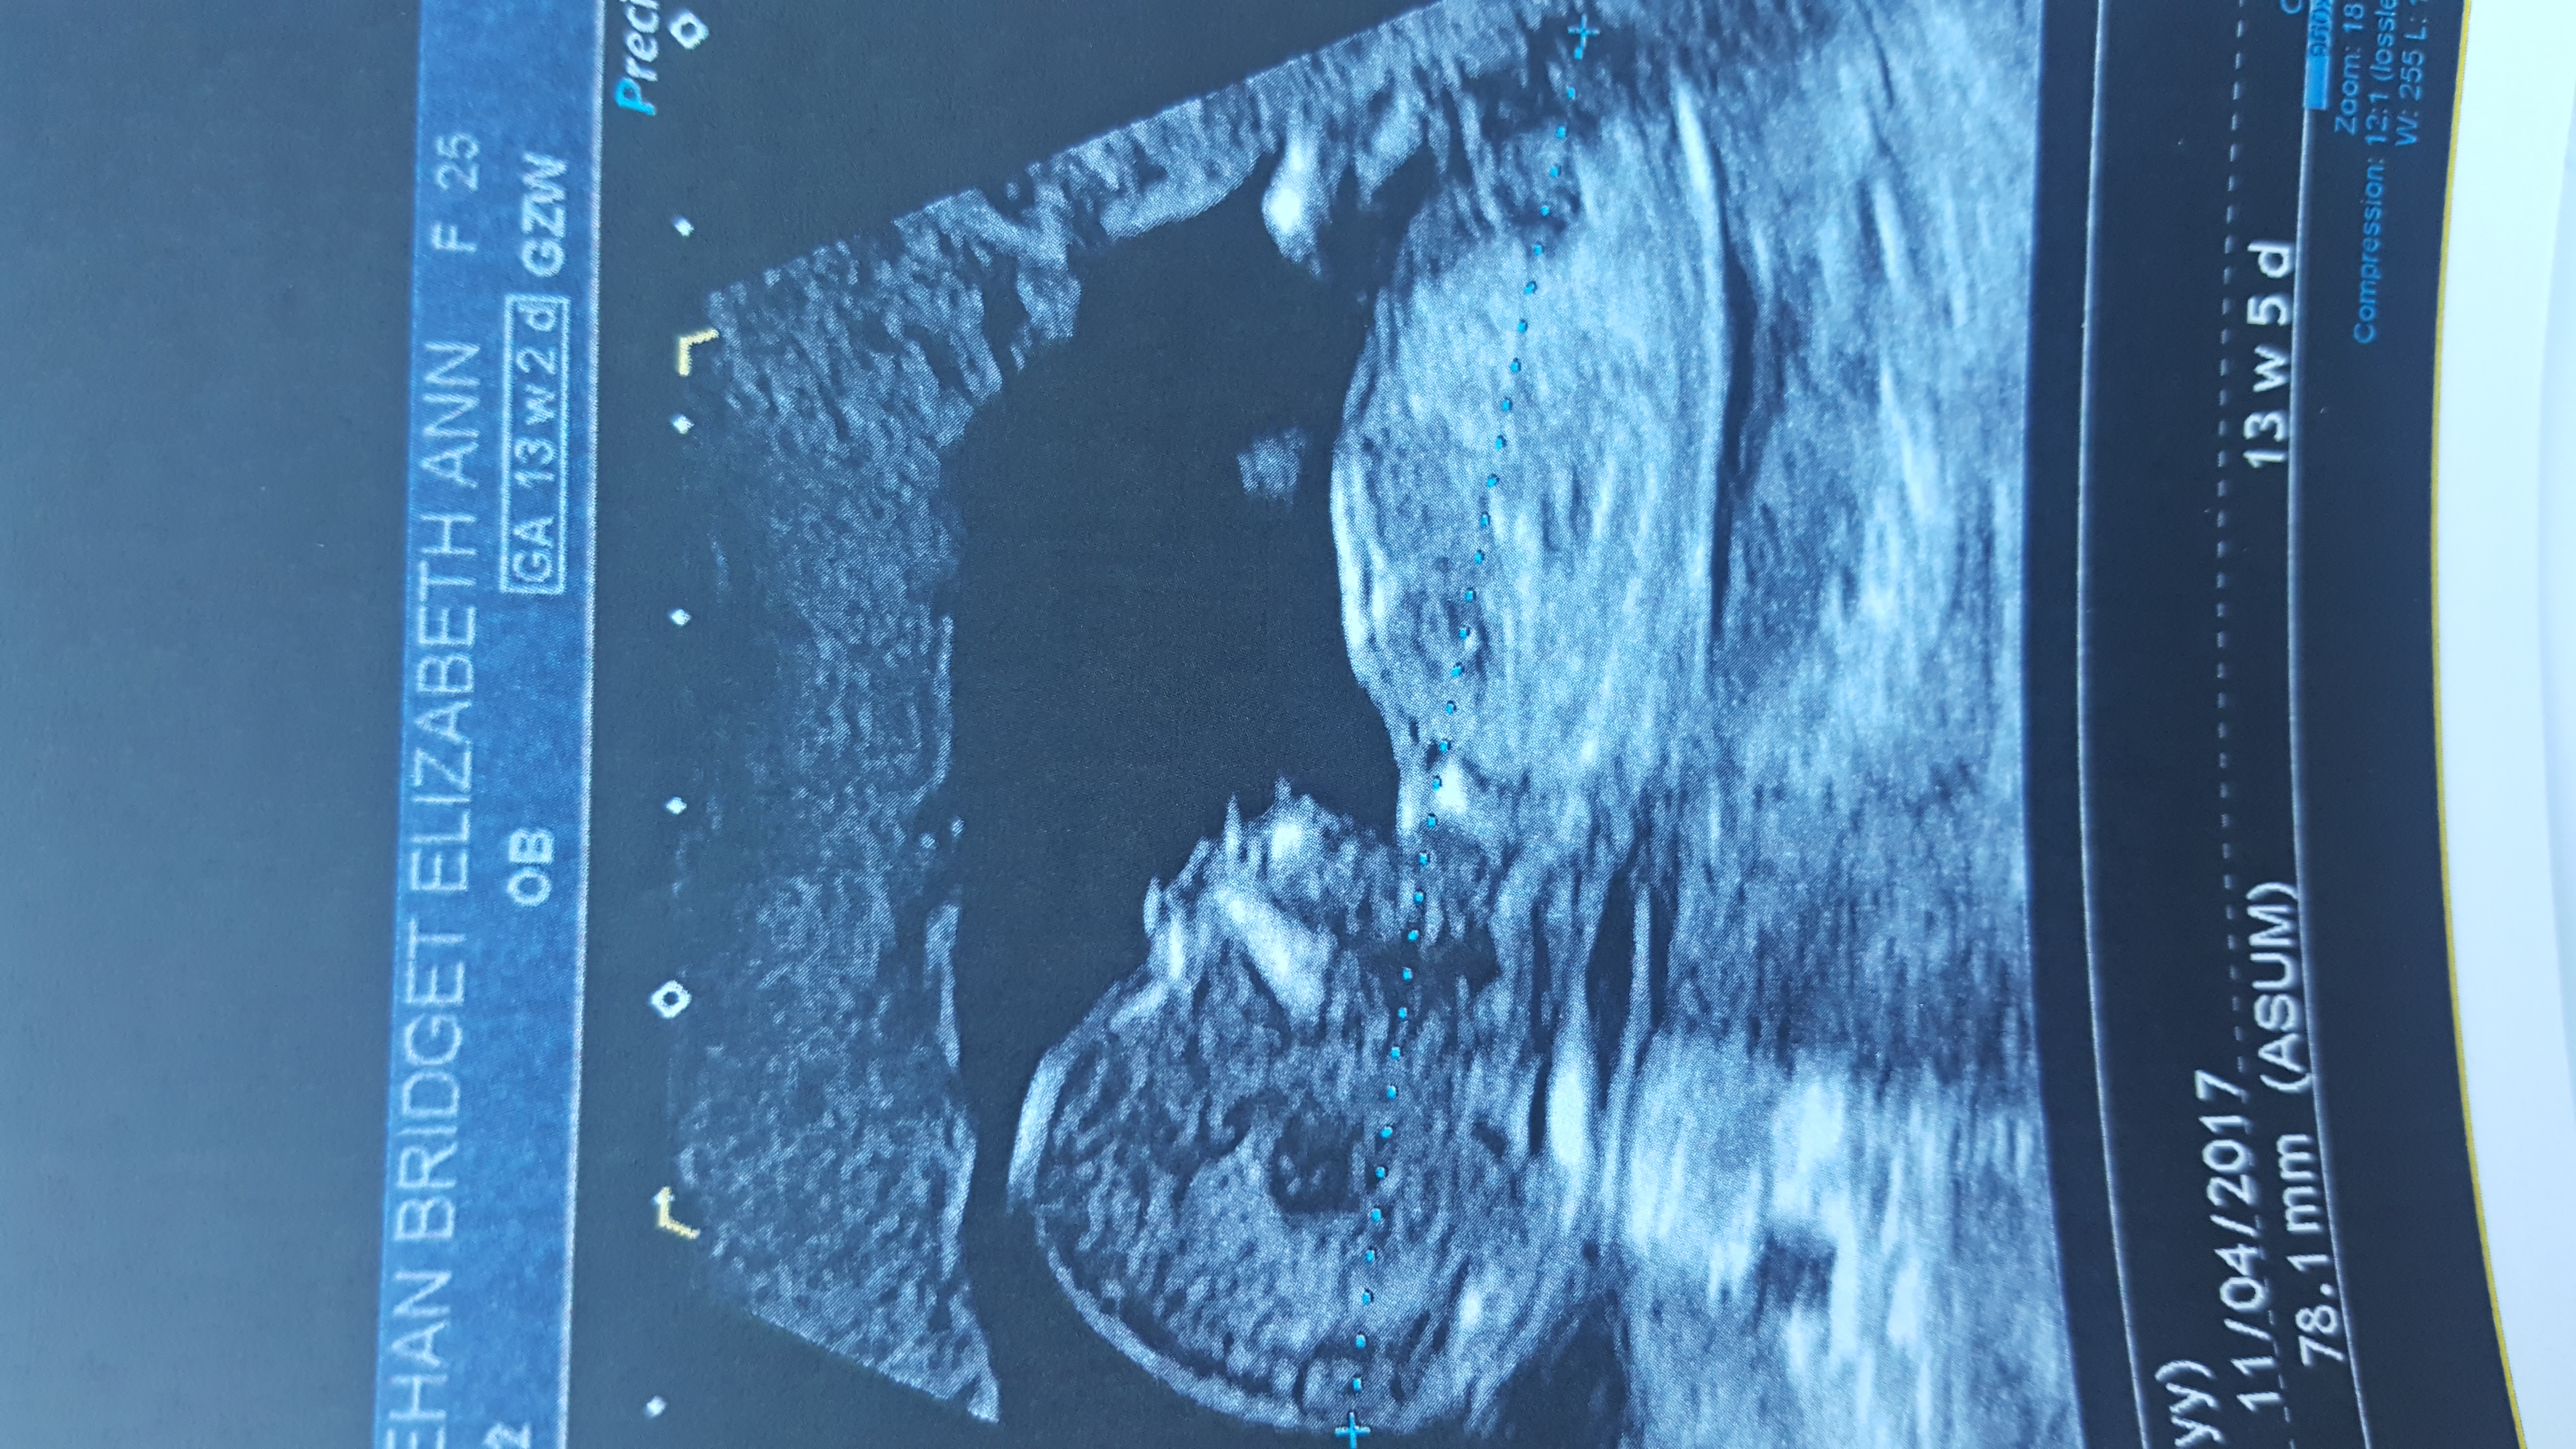

I am currently 13 weeks pregnant, well just over that and have had two scans in last three days due to baby playing up at scans. Wondering if anyone might be able to guess what gender baby is from these pictures as scan lady wouldn't check properly.

Attachment 33294Attachment 33295Attachment 33294Attachment 33295